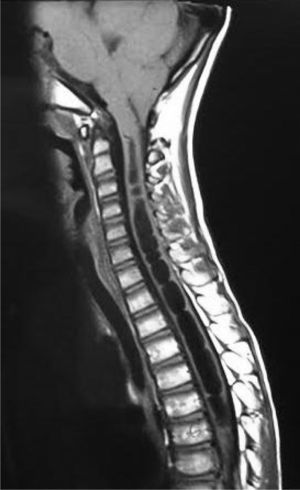

Se realizó una gammagrafía ósea de pelvis y MMII (fig. 1) sin alteraciones en caderas, mostrando menor captación derecha. Ante la sospecha de un proceso con afectación crónica del lado derecho, se realizó resonancia magnética cerebral y medular (figs. 2 y 3) y se diagnosticó de malformación de Arnold-Chiari tipo 1 (MCI) y siringomielia extendida hasta T8. El paciente fue derivado para intervención neuroquirúrgica que resultó exitosa.